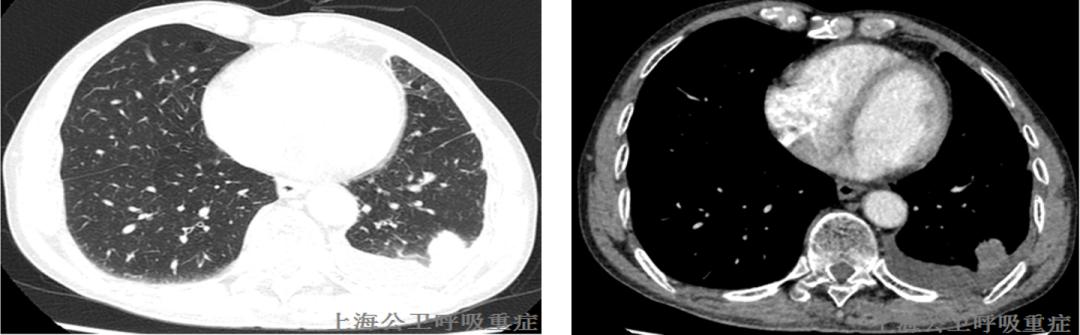

2020.12.01颈部CT增强示:右侧喉部软组织占位,两侧颈部多发肿大淋巴结,部分融合——考虑MT伴颈部淋巴结转移可能大,请进一步检查。

2020.12.02局麻下行经超声引导下颈部淋巴结穿刺术,术后病理报告:“右侧颈上部淋巴结穿刺”,见低分化癌组织转移,倾向鳞癌。

PET-CT(2020-12-18)结果提示:1、喉咽部团块伴FDG代谢增高,考虑恶性病变伴病灶周围、双侧颈部多发淋巴结转移。2、双肺肺气囊,左肺多发实性班片灶,FDG代谢增高,建议抗炎治疗后复查,双肺散在斑点、斑片灶、双侧肺门及纵隔淋巴结炎性增生可能。